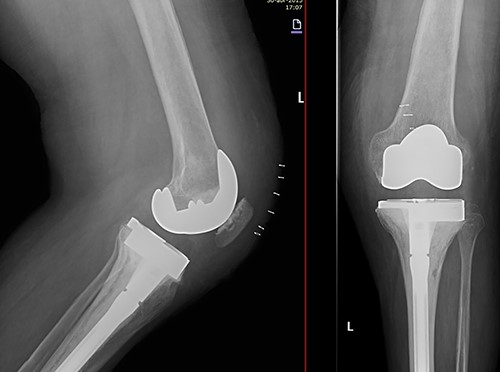

At this point, the patient was recovering from a respiratory infection with multiple admissions and relapses, with CD4 cell count of 146 cells/ml. Therefore, conservative treatment was recommended, but pain control was insufficient. After 8 months she was admitted to the emergency service in a wheelchair due to intractable acute pain without prior trauma in the left knee, which prevented weight-bearing. New standing X-rays of the left knee showed collapse of the external tibial plateau (Fig. 2). At this time, the patient exhibited acceptable medical control, with CD4 240 cells/ml and undetectable viral load.

Standing X-rays of the left knee 8 months later showed collapse with depression of the external tibial plateau and associated bone defect that caused 28° valgus deformity.

Due to the poor bone quality and defect associated to osteonecrosis (Fig. 3), osteosynthesis was discarded and total knee arthroplasty (TKA) was performed with lateral tibial block and diaphyseal stem (Fig. 4). Microbiological samples confirmed the absence of infection. Pathological samples confirmed osteolysis and chronic synovitis with osteoporosis and osteonecrosis, leading to the pathological fracture (Figs 5 and 6).

X-ray of the left knee showing reconstruction with 10-mm tibial lateral block and a tibial diaphyseal stem.